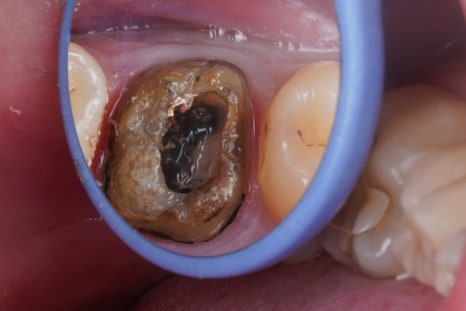

크라운을 벗겨내고

치아 내부를 관찰해봅니다.

굉장히 지저분하죠

크라운 내부, 치아의 외면은 물론

신경치료했던 치아 내부 역시

많이 오염되어있었습니다.

치과적인 통증은

외상을 제외하면 대부분

세균과의 싸움입니다.

infection control, 감염조절이

신경치료 성공의 핵심인데요,